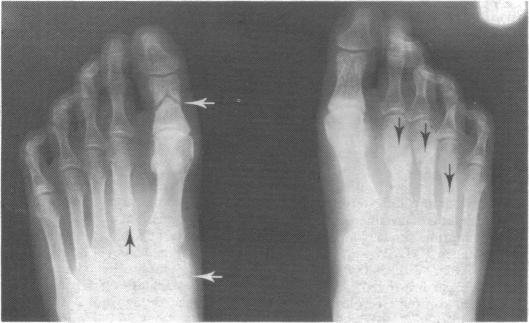

Among 39 patients treated by regular haemodialysis for four years or more pathological fractures and histological evidence of osteomalacia were significantly more common in those taking barbiturates. Out of 58 transplant recipients surveyed after one year, seven had osteomalacia; four of these had been taking phenobarbitone and phenytoin and one had taken barbiturates alone. Sedatives and other drugs such as phenobarbitone and phenytoin that induce hepatic microsomal enzymes should probably be avoided when possible in patients with chronic renal failure and after transplantation.